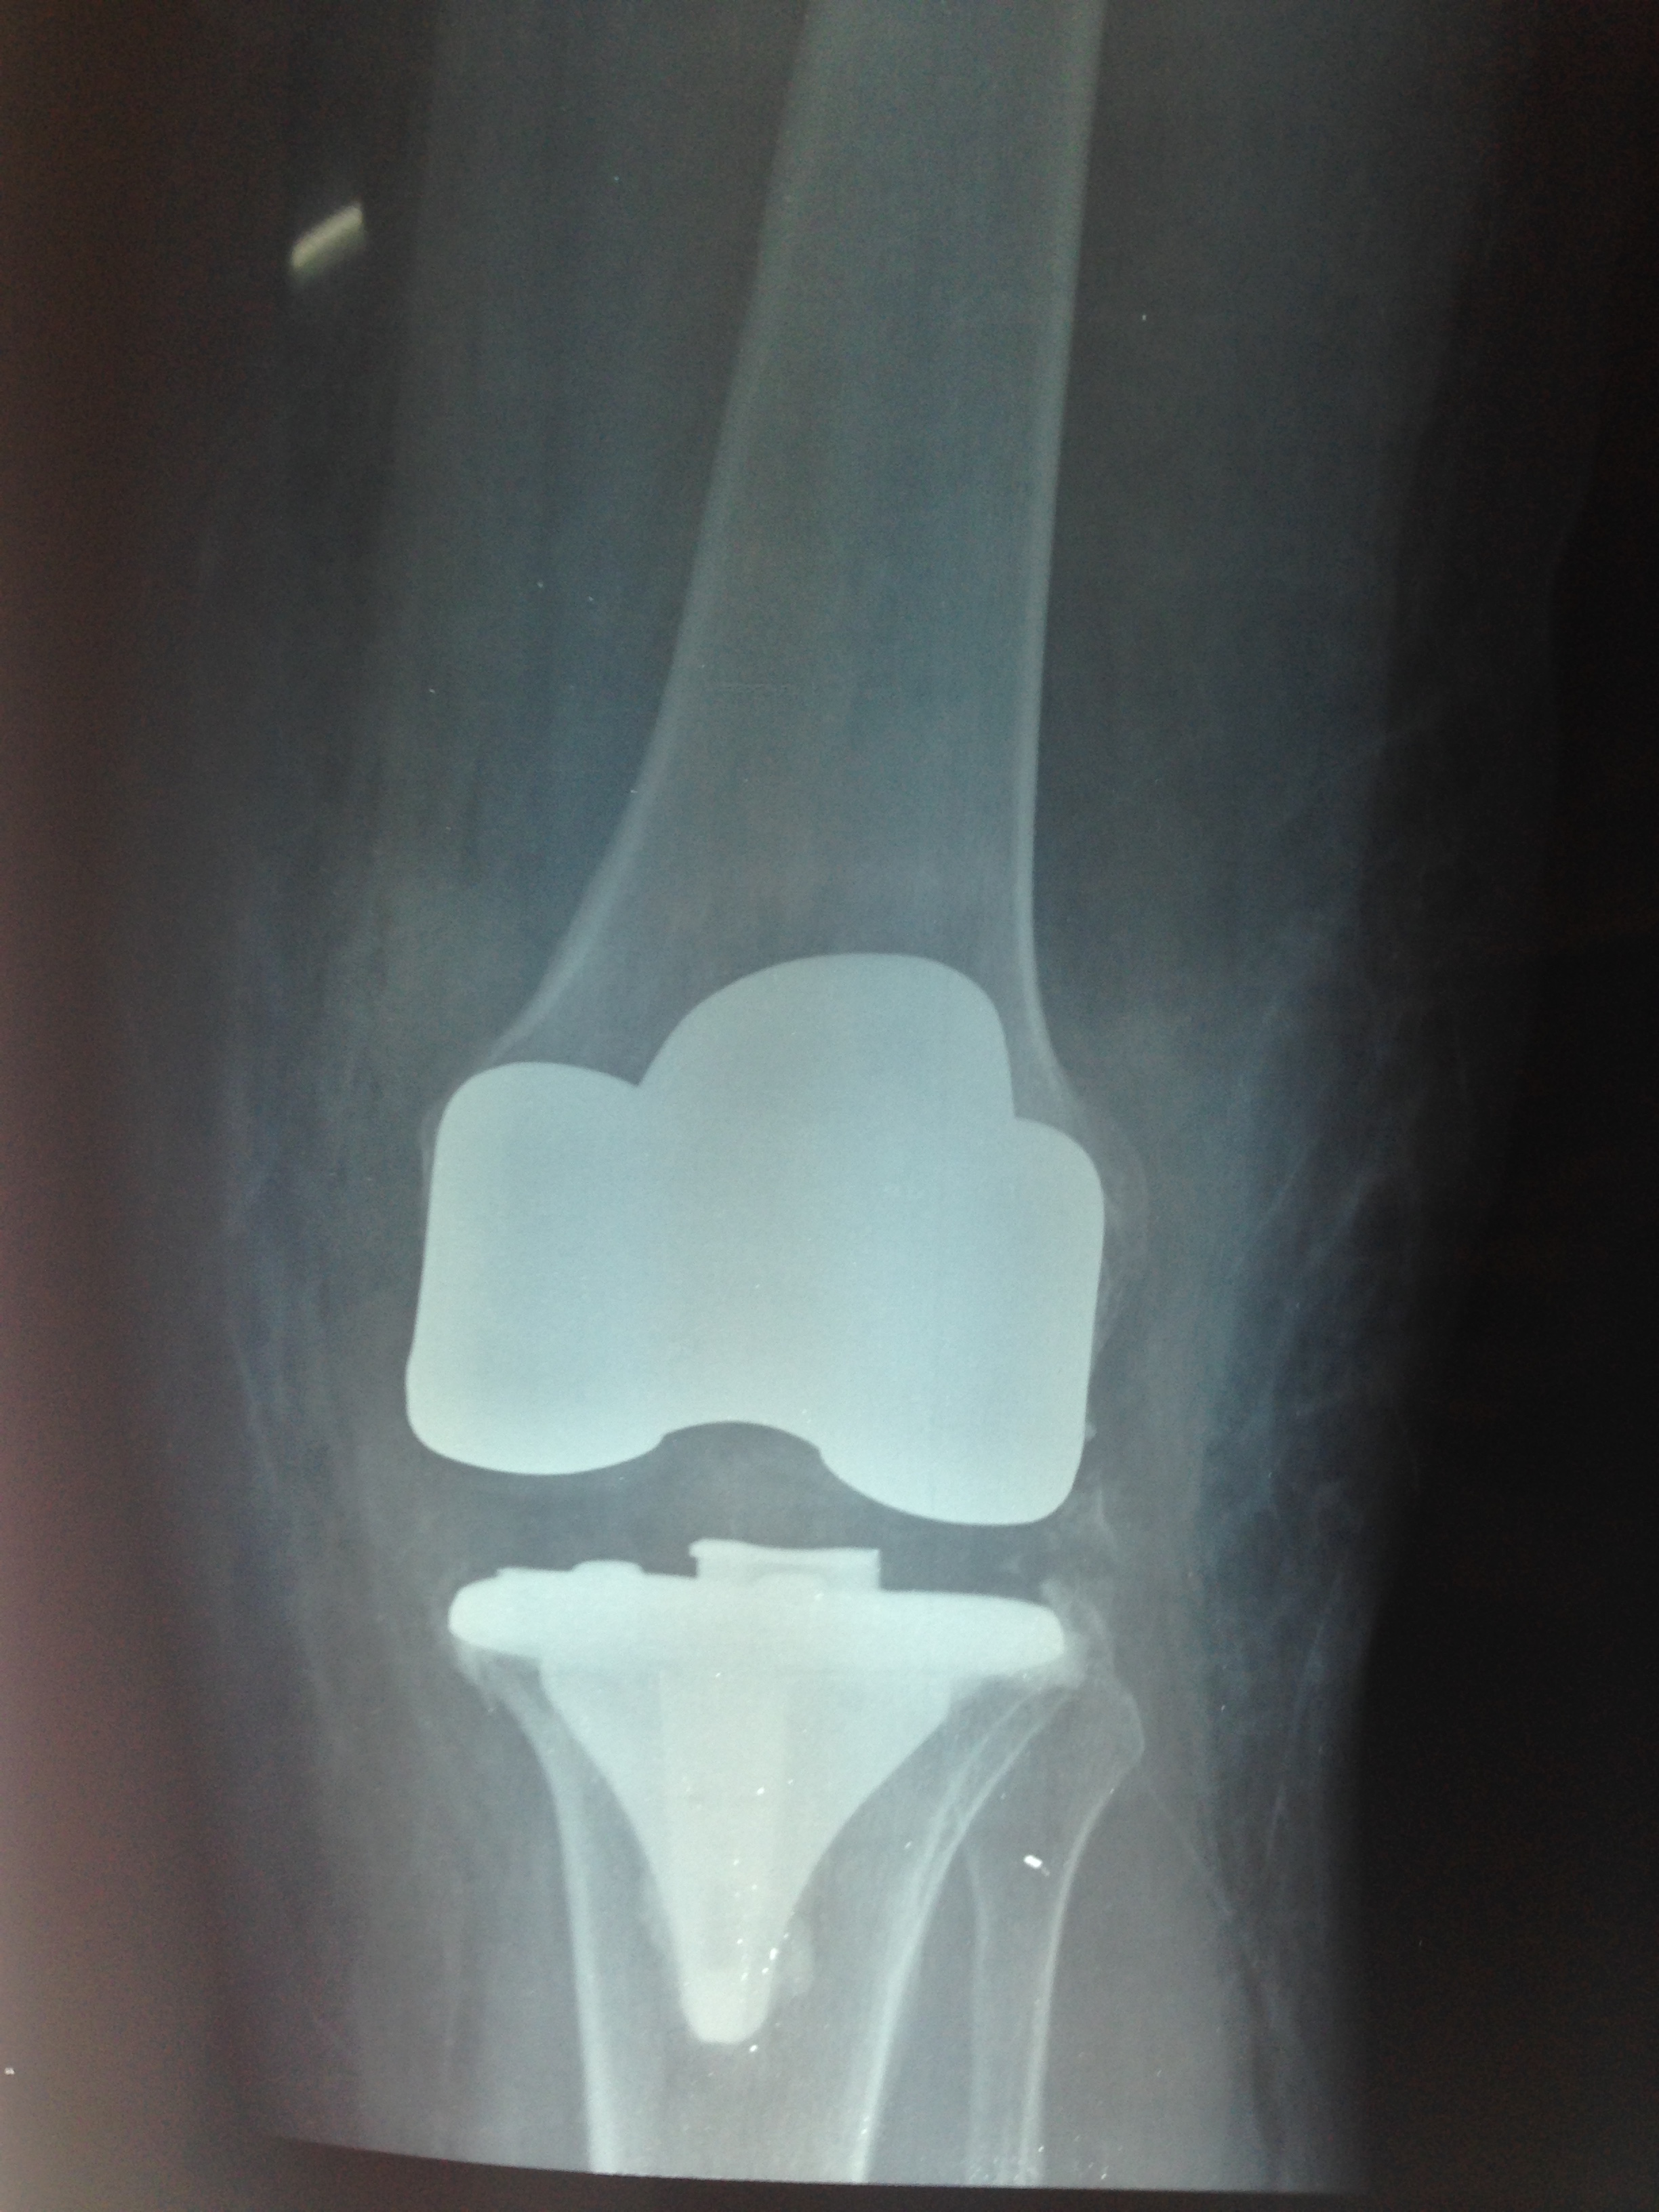

Prótesis Total de Rodilla

La Prótesis Total de Rodilla (PTR) es una cirugía de reemplazo articular que consiste en la sustitución de la articulación de la rodilla por elementos protésicos. Consiste en el reemplazo de la superficie articular del fémur, la tibia y la rótula y tiene como objetivo restablecer la función y aliviar el dolor en situaciones como la artrosis de rodilla.

Las prótesis más habituales son las totales o las parciales (también llamadas unicompartimentales). Los componentes más utilizados consisten en aleaciones de cromo - cobalto - molibdeno y un componente de polietileno en el lado tibial de la articulación. La incisión que se utiliza con más frecuencia para esta cirugía es la localizada en la cara anterior de la rodilla.

Luego de la cirugía se indica a los pacientes la movilización precoz de la articulación y la deambulación progresiva con ayuda externa (andador o bastón) siempre bajo la supervisión inicial de un rehabilitador.